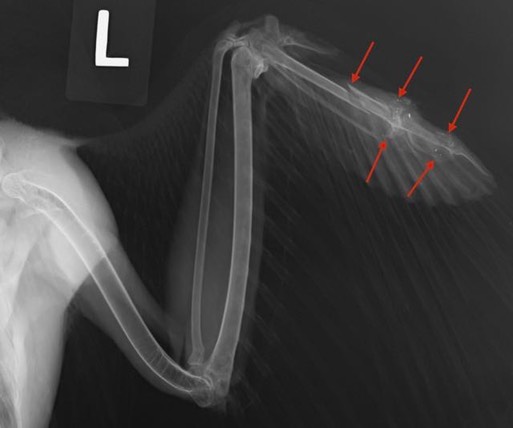

Unfortunately, an exam and radiograph found the hawk had been shot, the fifth gunshot bird admitted this year. There are multiple fractures in the left wingtip and most of the primary feathers in the left wing are broken. We are hopeful he will be releasable, but he will have to molt the broken feathers and grow new ones before we will know for sure.